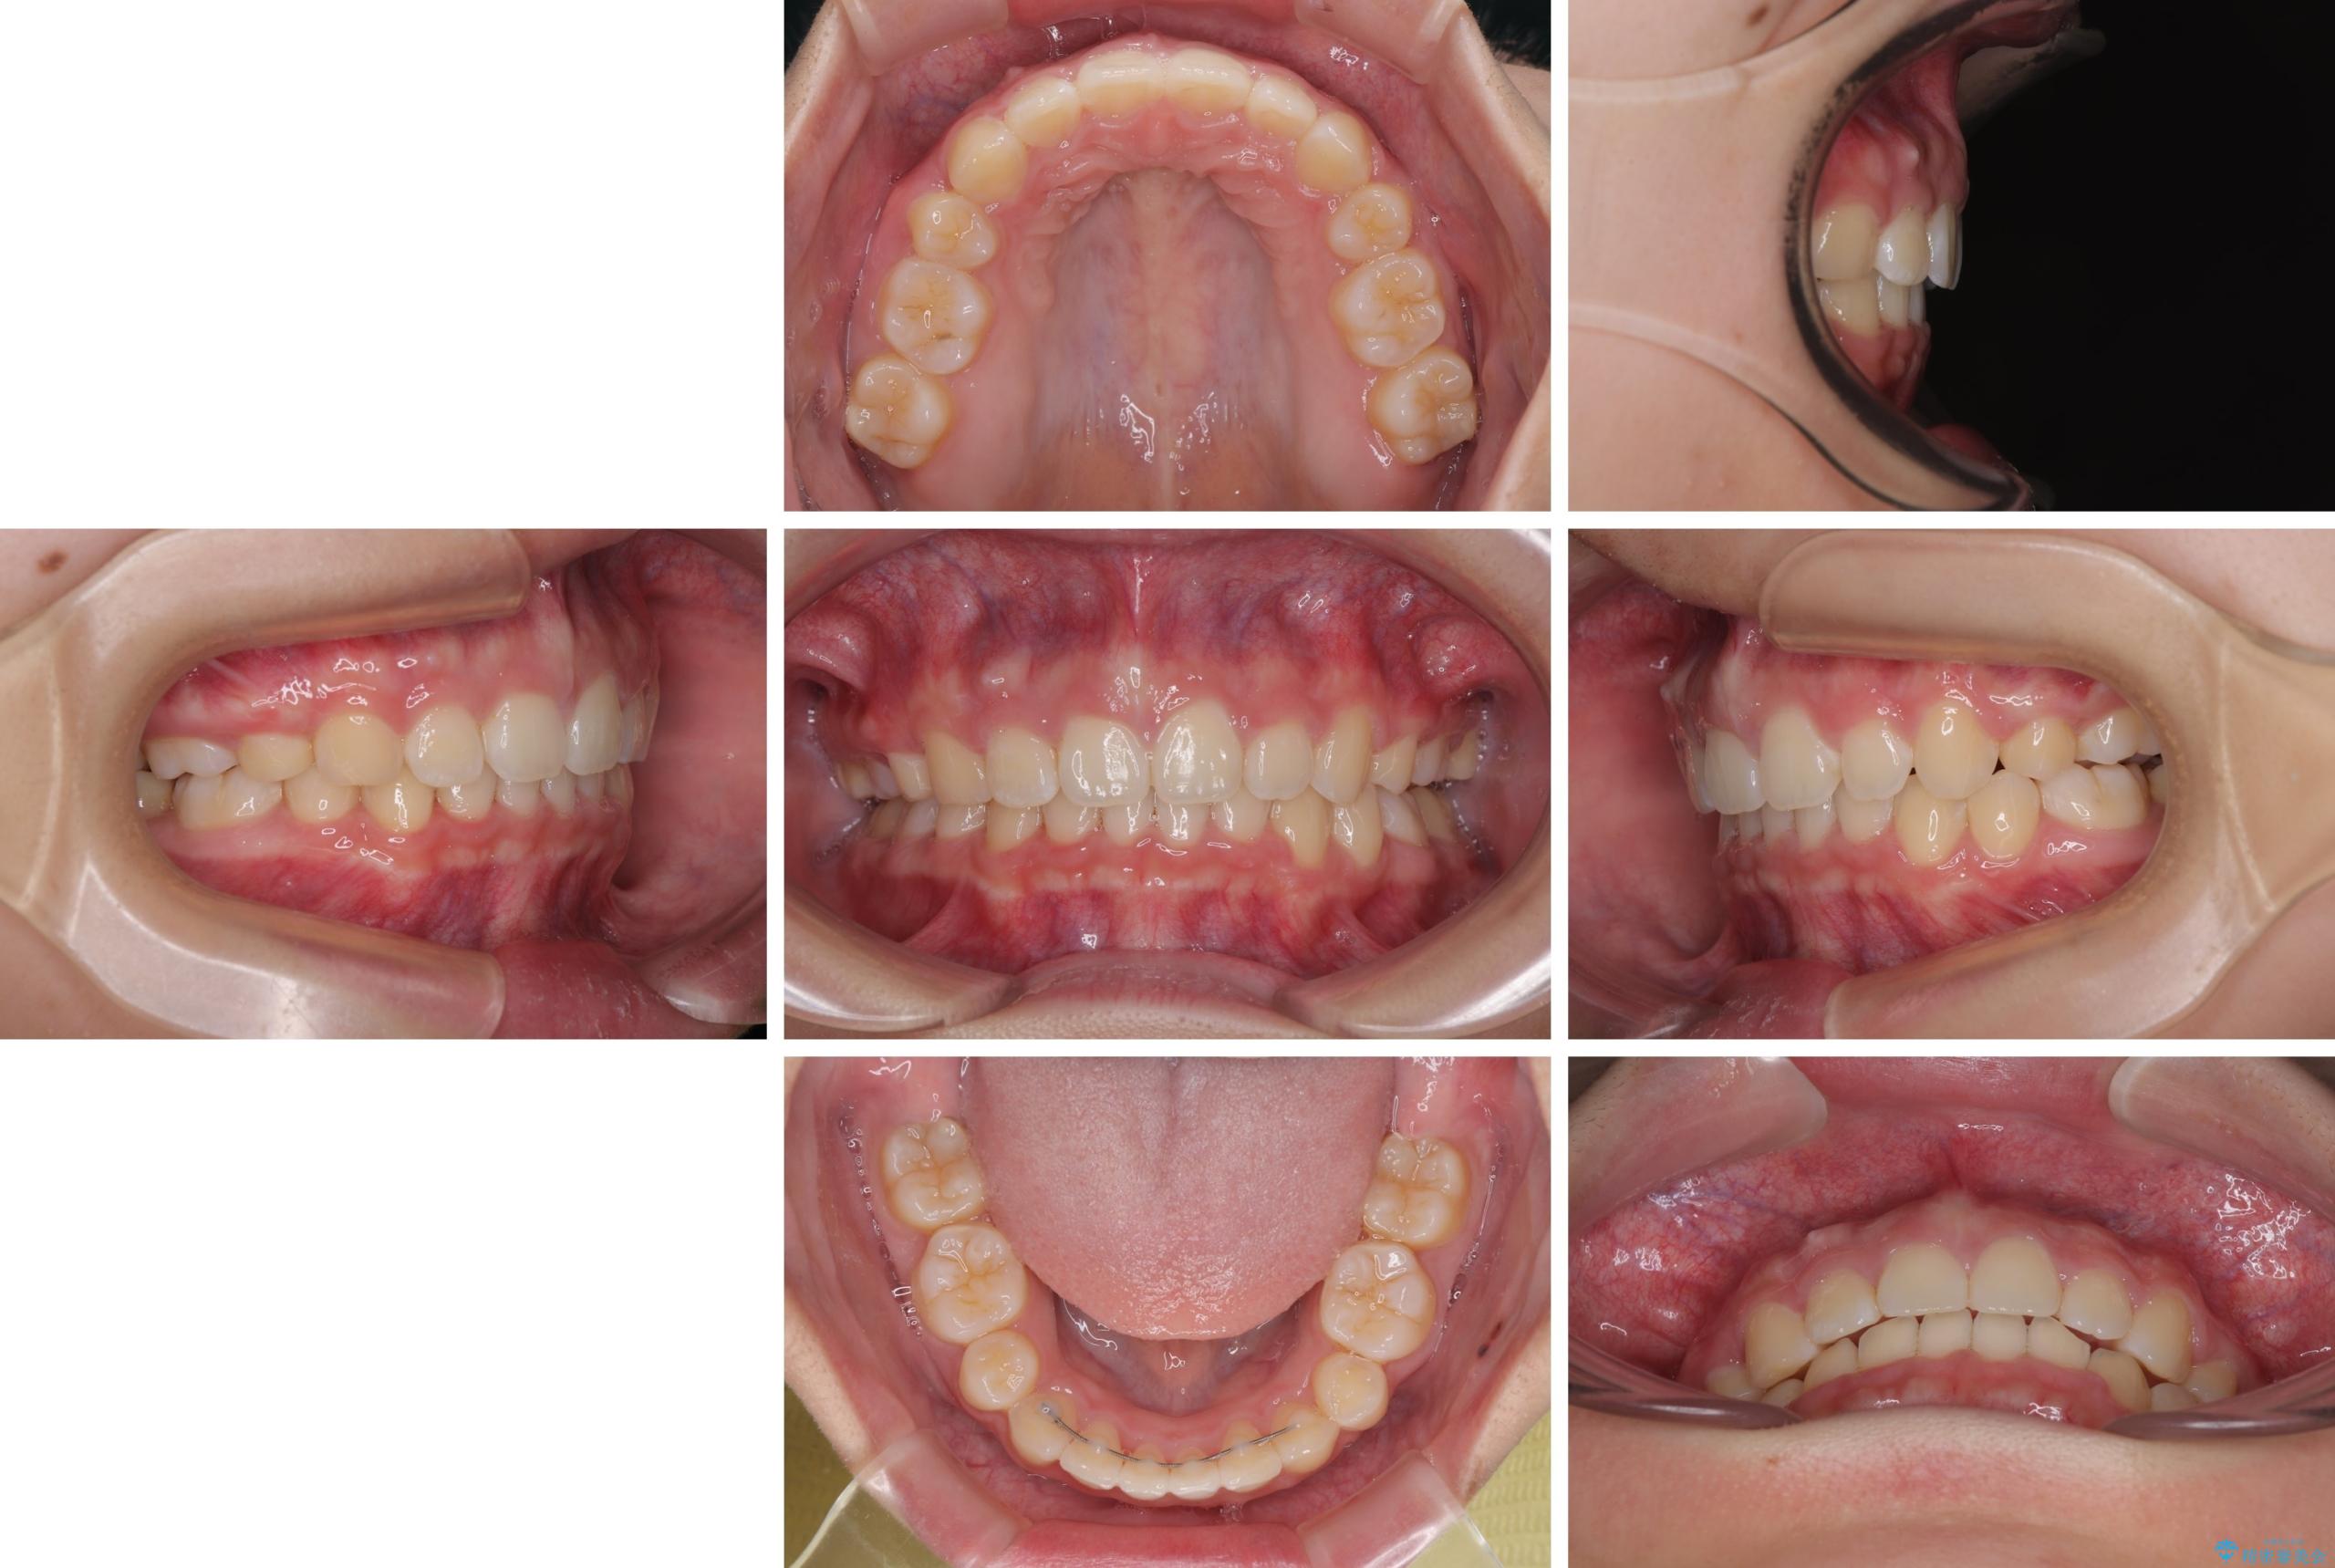

- 上顎前歯が飛び出していて唇がうまく閉じられないとのことで来院された患者様です。

くちばしのように前歯が突出していたため、口元を積極的に引っ込めるために、上下左右の小臼歯4本を抜歯することとしました。

また、上顎歯列が下顎に対して前方位に位置していたため、補助装置を用いて上顎歯列を後方に移動させ、より積極的に口元を下げるようにしました。

上下正中位置を改善するため、左下はイレギュラーに第二小臼歯を抜歯しました。そのため治療期間の長期化が予想されましたが、2年半ほどで期待通りの歯列に仕上げることができました。